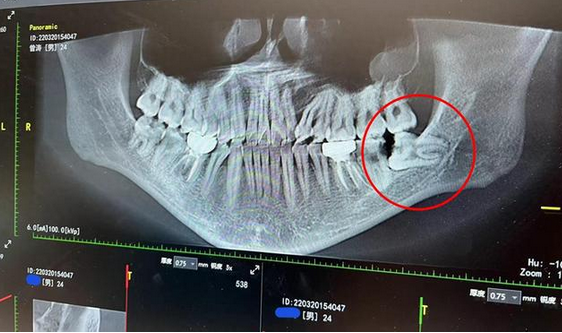

哪种人拔牙后更容易得"干槽症"?得了之后还能治好吗?

干槽症又称局限性牙槽骨炎,纤维蛋白溶解性